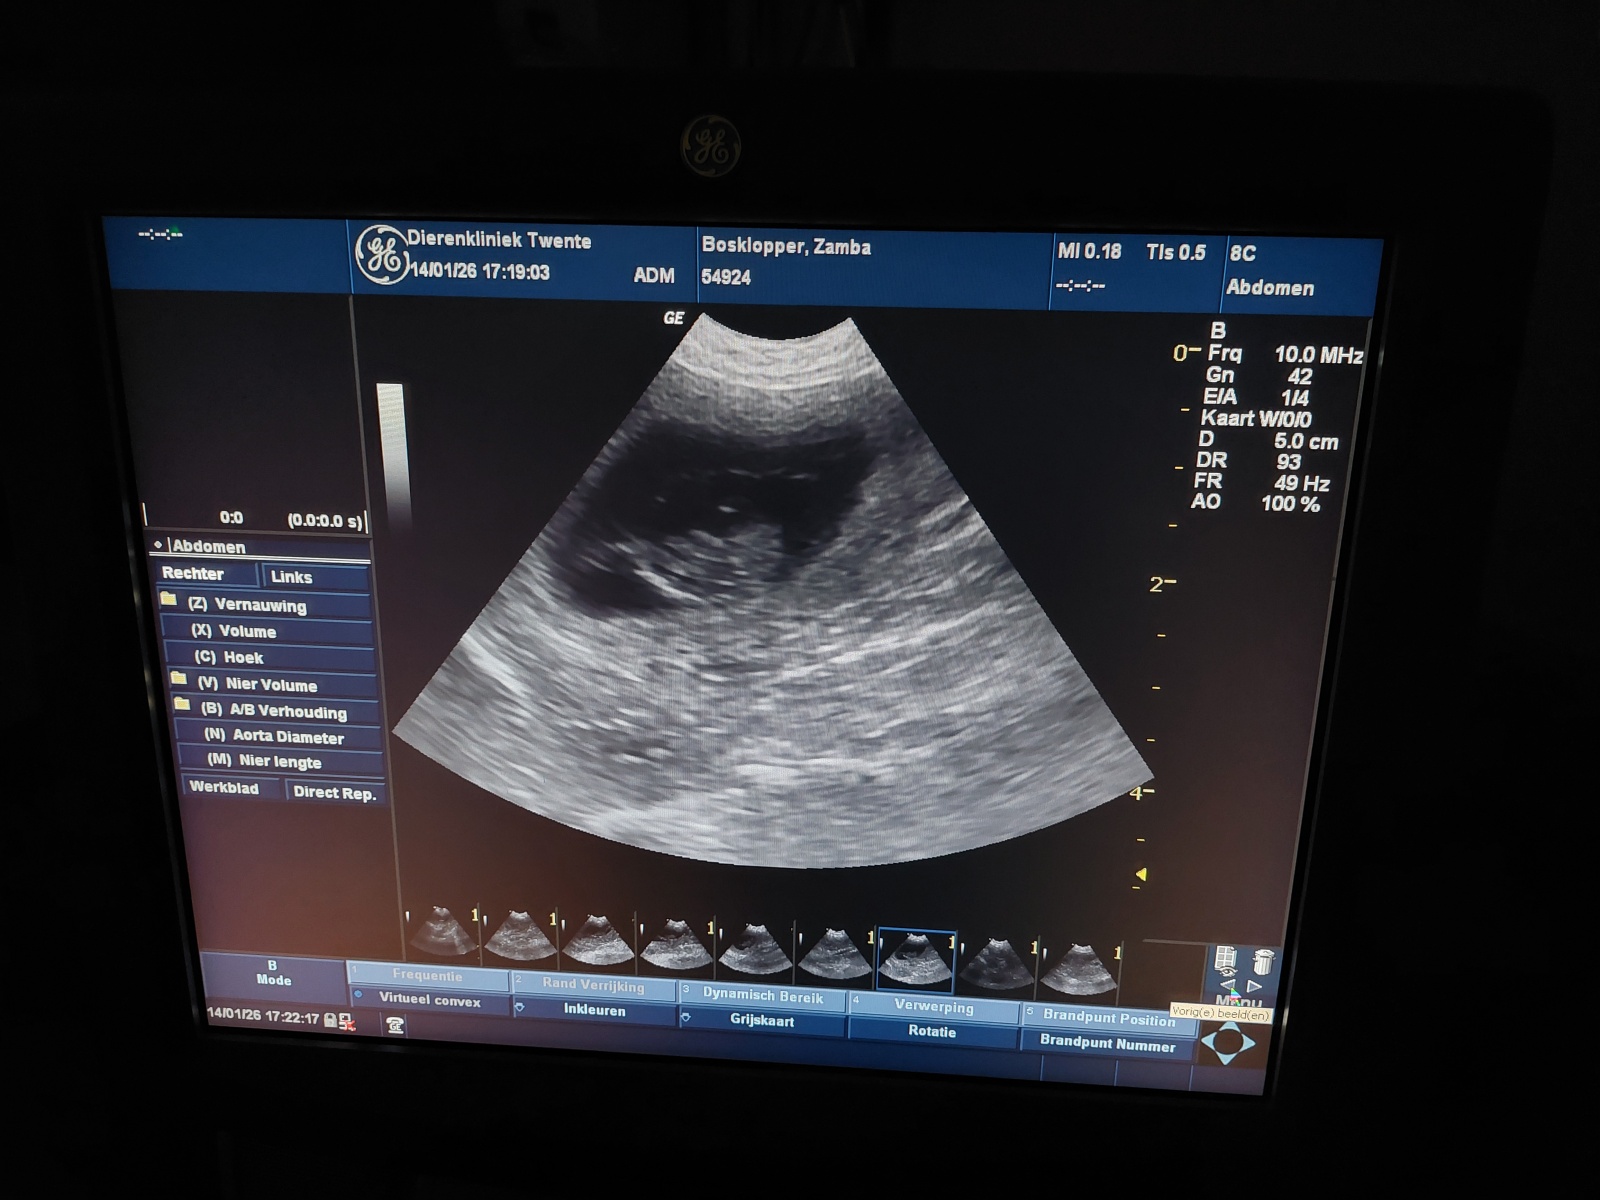

Op 14 januari 2026 is bij Dierenkliniek Twente in Enschede een echo gemaakt van Dazzling Flash Zamba. Tijdens dit onderzoek werd bevestigd dat zij dragend is. Alles ziet er op dit moment goed en gezond uit.

Op basis van de echo is de verwachting dat er waarschijnlijk vier pups onderweg zijn. Een echo blijft altijd een momentopname, maar de bevindingen geven een positief en geruststellend beeld van het verloop van de dracht tot nu toe.

Echo van de dracht bij Dazzling Flash Zamba, januari 2026Echo van de dracht bij Dazzling Flash Zamba, januari 2026